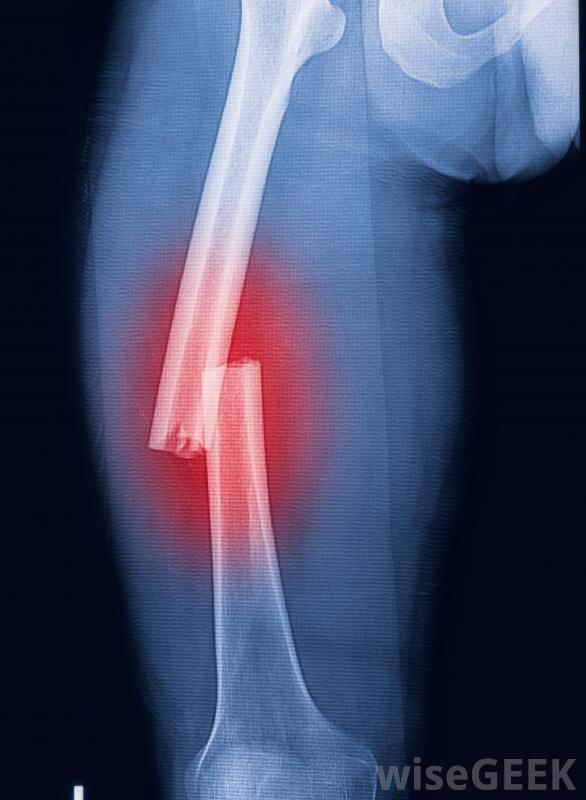

骨密度低的原因是什么(Causes of Low Bone Density)?

低骨密度可能與衰老、疾病、環境因素和生活方式有關。有低骨密度風險的患者通常很容易識別,允許醫生推薦一些預防骨質流失和重建骨骼的措施。這些預防和治療措施可以包括溫和的運動、飲食調整和一些生活方式的改變,這取決于患者被認為有風險的原因宇航員在太空中必須進行鍛煉,以防止骨骼變弱,低雌激素水平會導致骨密度下降。年輕的女運動員可能會面臨風險,因為她們通常很瘦,體重也很低。絕經后的老年婦女也會受到關注,因為她們的激素水平會隨著更年期的變化而變化。激素紊亂和體內高水平的皮質類固醇激素也可能是背后的罪魁禍首骨密度降低,尤其是女性。隨著年齡的增長,骨骼變得更加脆弱,更容易斷裂暴露于輻射是另一個危險因素,這是宇航員最常擔心的問題,因為盡管有防護罩,但宇航員在太空工作時輻射水平很高航天員經常被評估是否有低骨密度的跡象,他們在太空中的時間是定量的,以減少與輻射接觸有關的永久性損傷的風險。在有輻射的環境中工作的人也會受到高輻射照射的監測白種人和亞洲人天生就有低密度的危險。生活方式導致低骨密度的原因包括運動受限、吸煙,過度飲酒。飲食也是一個因素。飲食失調和營養不良使人們更難形成和保持骨骼。此外,某些藥物也可能導致骨密度的下降。隨著年齡的增長,他們的骨骼往往比身體重建骨骼的速度要快。這一過程可能會因某些肌肉骨骼疾病而加速。患有骨骼和關節疼痛、肌肉無力和疲勞的人可能需要評估骨骼的醫療狀況。如果擔心骨密度低,建議服用膳食補充劑和物理療法來維持骨骼強度,并隨著時間的推移重建骨骼。骨密度的降低是一個嚴重的問題。患者嚴重骨折的風險增加,尤其是像臀部這樣的主要骨骼,骨折后愈合需要更長的時間,也會出現骨痛和虛弱,使日常活動困難,活動受限。